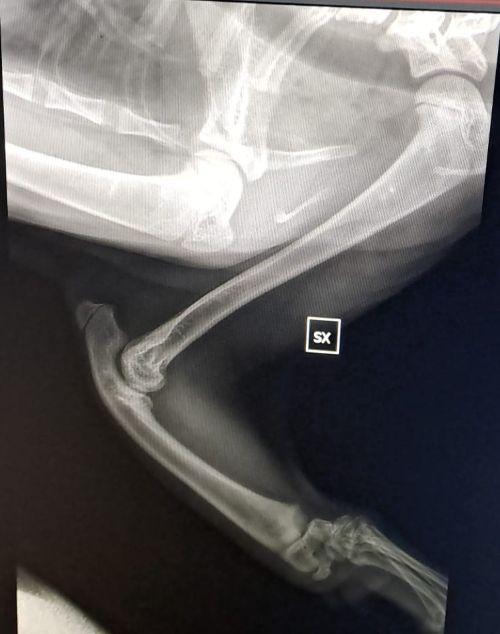

Vor drei Tagen bekamen wir die ersehnten Untersuchungsergebnisse für Pino. Seine Vorderbeine wurden in mehreren Schichten geröntgt und das Ergebnis muss man erstmal verdauen.

Es war sehr stark zu erwarten, dass es sich um eine angeborene Anomalie handelt. Und dies ist auch so. Pinos „Speichenknochen“ (Radius) fehlen auf der linken Seite ganz, auf der rechten Seite ist er unterentwickelt. Das führt dazu das seine Füßchen mit den Ellenbogen nicht stabil verwachsen sind und die Gelenke nicht festsitzen. Dadurch wachsen auch die Knochen nicht entsprechend und haben krankhafte Veränderungen. Der kleine Mann wird seine Vorderbeine nie richtig belasten können, so wie es im Moment aussieht. Ein normales Katzenleben in Freiheit ist für ihn in diesem Zustand unmöglich. Gott sei Dank zeigen sich aber keine andere Anomalien in seiner Anatomie.

Sofort nach der Diagnose haben wir begonnen uns in Spezialkliniken in Deutschland umzuhören, um einen fachmännischen Rat zu bekommen. Wenn Pinos Wachstum abgeschlossen ist, gibt es chirurgische Möglichkeiten, Fuß- und Ellenbogen Gelenke zu stabilisieren. Dies ist aufwändig und nur von Spezialisten durchführbar.